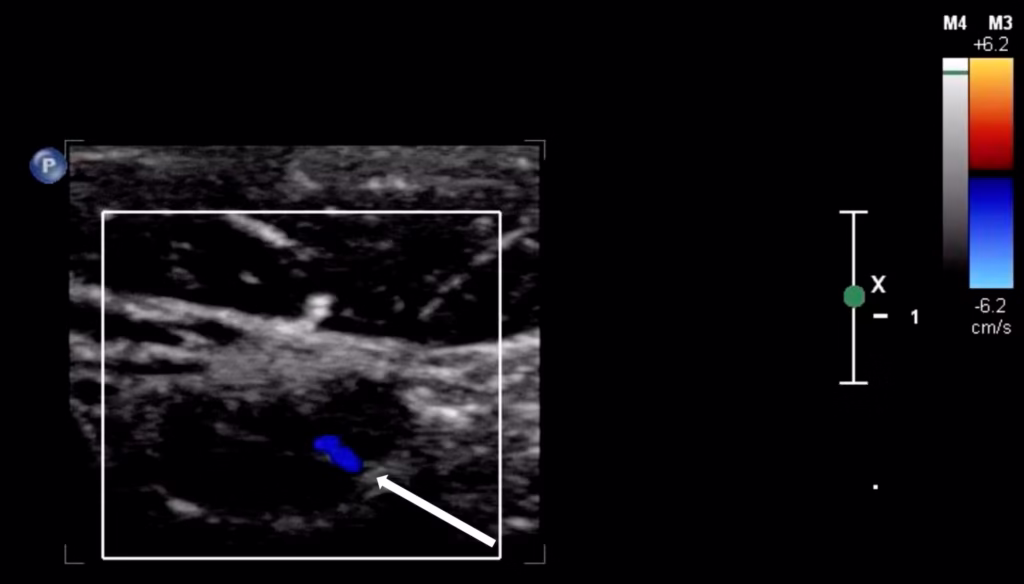

POCUS of the skin and soft tissues was performed by a board-certified pediatric emergency medicine attending with emergency ultrasound fellowship training on a GE Venue machine (Waukesha, WI, USA), using a 4.2-13.0 MHz linear probe in a musculoskeletal preset. The POCUS examination revealed multiple bilateral hypoechoic ovoid structures with no identifiable hilum, the largest of which measured 1.9 cm in diameter (Figure 2). There was also markedly increased internal vascularity in a “fire-like” distribution within all the involved structures on color Doppler (Figure 3). Additionally, the POCUS examination demonstrated posterior acoustic enhancement, increased echogenicity of the surrounding soft tissue, and superficial cobblestoning (Figure 4). These POCUS findings, along with the notable absence of gut signature, internal heterogeneity, or free fluid, facilitated the identification of lymphadenopathy. The presence of posterior acoustic enhancement, increased echogenicity of surrounding soft tissues, and increased vascularity on color Doppler, in combination with physical examination findings of tenderness, warmth, and overlying erythema, were suggestive of infectious lymphadenitis with surrounding cellulitis.

Figure 3. Point of care ultrasound (POCUS) with color Doppler. Diffuse internal vascularity is shown, previously described as “fire pattern.”

Sonographic features of lymphadenopathy due to CSD have been previously described in the literature. García et al. reported the ultrasonographic findings in 47 patients diagnosed with CSD who underwent a radiology-performed skin and soft tissue ultrasound [4]. They noted multiple findings that were present in a majority of patients in the series, including the presence of three or more enlarged lymph nodes (91%), hypoechoic echotexture (100%), posterior acoustic enhancement (89%), and increased echogenicity of surrounding soft tissues (100%) [4]. The POCUS examination that was performed in our case demonstrated each of these characteristic findings. Additionally, all 21 cases in the García et al. series that were evaluated with color Doppler demonstrated “highly vascularized lymph nodes” with a loss of the typical vascular architecture. García et al. coined the term “fire pattern” to describe the diffuse color Doppler signal observed within the enlarged lymph nodes and postulated that this pattern was due to neovascularization associated with Bartonella infection [4]. We observed a similar distribution of Doppler signal in our case (Figure 3).